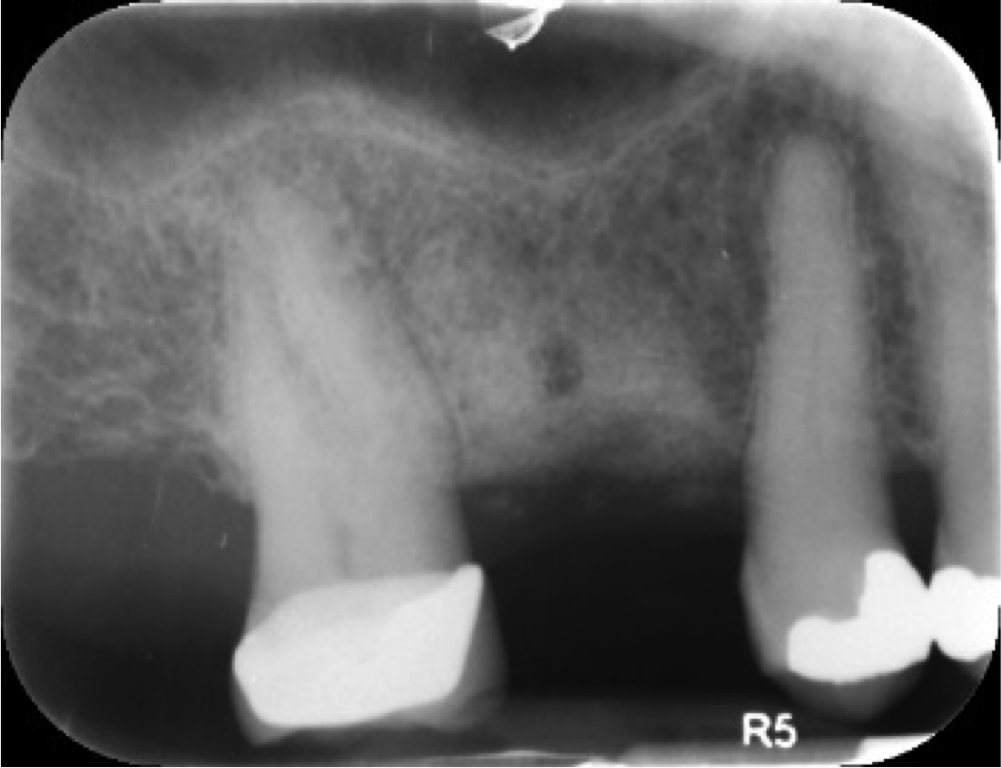

Fig 6. Periapical radiograph, single missing tooth.

Figure 6

The patient wanted an implant-supported crown to restore the right mandibular first molar, which had been extracted after recurrent caries, endodontic treatment, and development of a periapical lesion. The site was grafted with bone grafting material and a biological membrane and allowed to heal for 6 months. A periapical radiograph was then taken (Figure 6), which showed the socket areas to be well condensed, with mature-looking bone. A CBCT scan was taken to facilitate implant-placement planning.